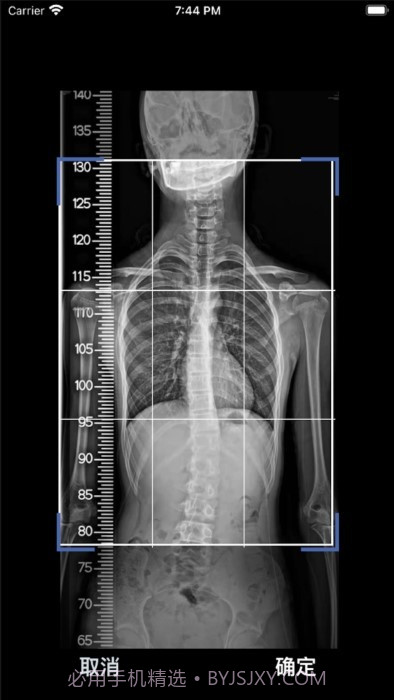

个人觉得,这款cobb角测量分析平台简直是医生和脊柱侧弯患者的福音!🌟 通过智能测量功能,能够迅速获取cobb角,准确率高得让人放心。对于有脊柱健康需求的小伙伴们来说,了解自己的状况特别重要,不仅能省时省力,更能随时存储和导出数据,后续分析也是轻松搞定!总之,这款应用为提高医疗效率、帮助患者掌握健康状况提供了强有力的支持,真心推荐给大家!

智能测量功能超赞,帮你快速获取cobb角,省时省力!

AI自动识别椎骨,准确率95%,不怕测错!